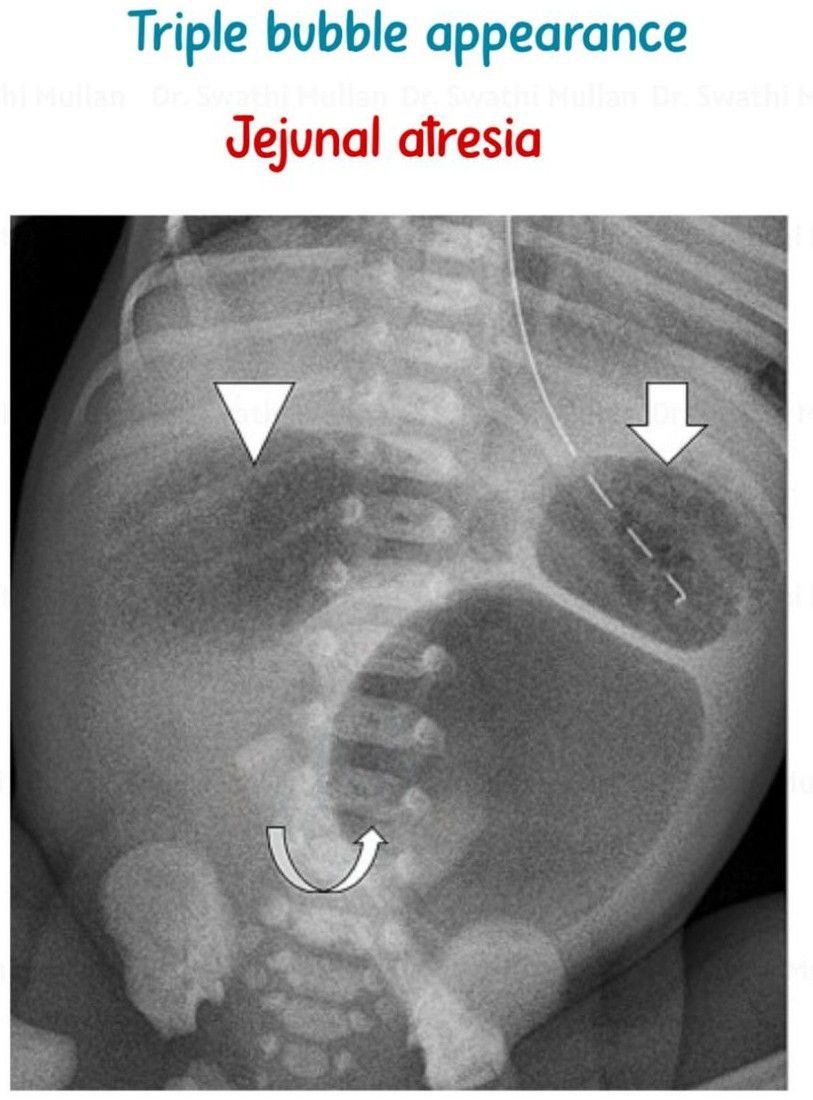

Triple Bubble Appearance

Can you name the conditions in which this appearance is seen?